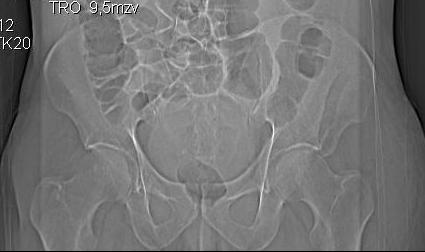

Уважаемые коллеги! Хотелось бы услышать ваше мнение. Мужчина 50л поступил с переломами костей таза. Закрытый перелом крыла подвздошной кости, переднего края вертлужной впадины справа.

Достаточно ли консервативного лечения, стоит ли беспокоиться о переднем крае? В приложении КТ.